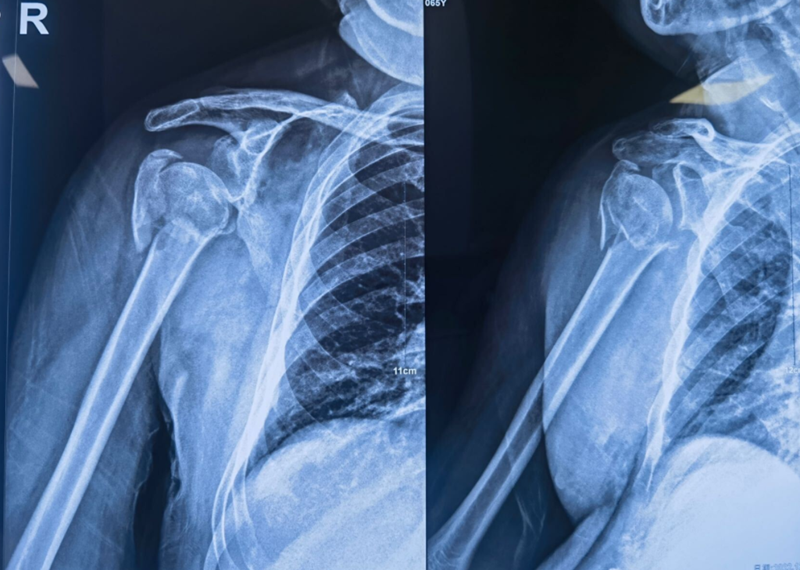

Xxx,男,65岁,右肱骨近端四部分骨折一周。

图16 术前X片